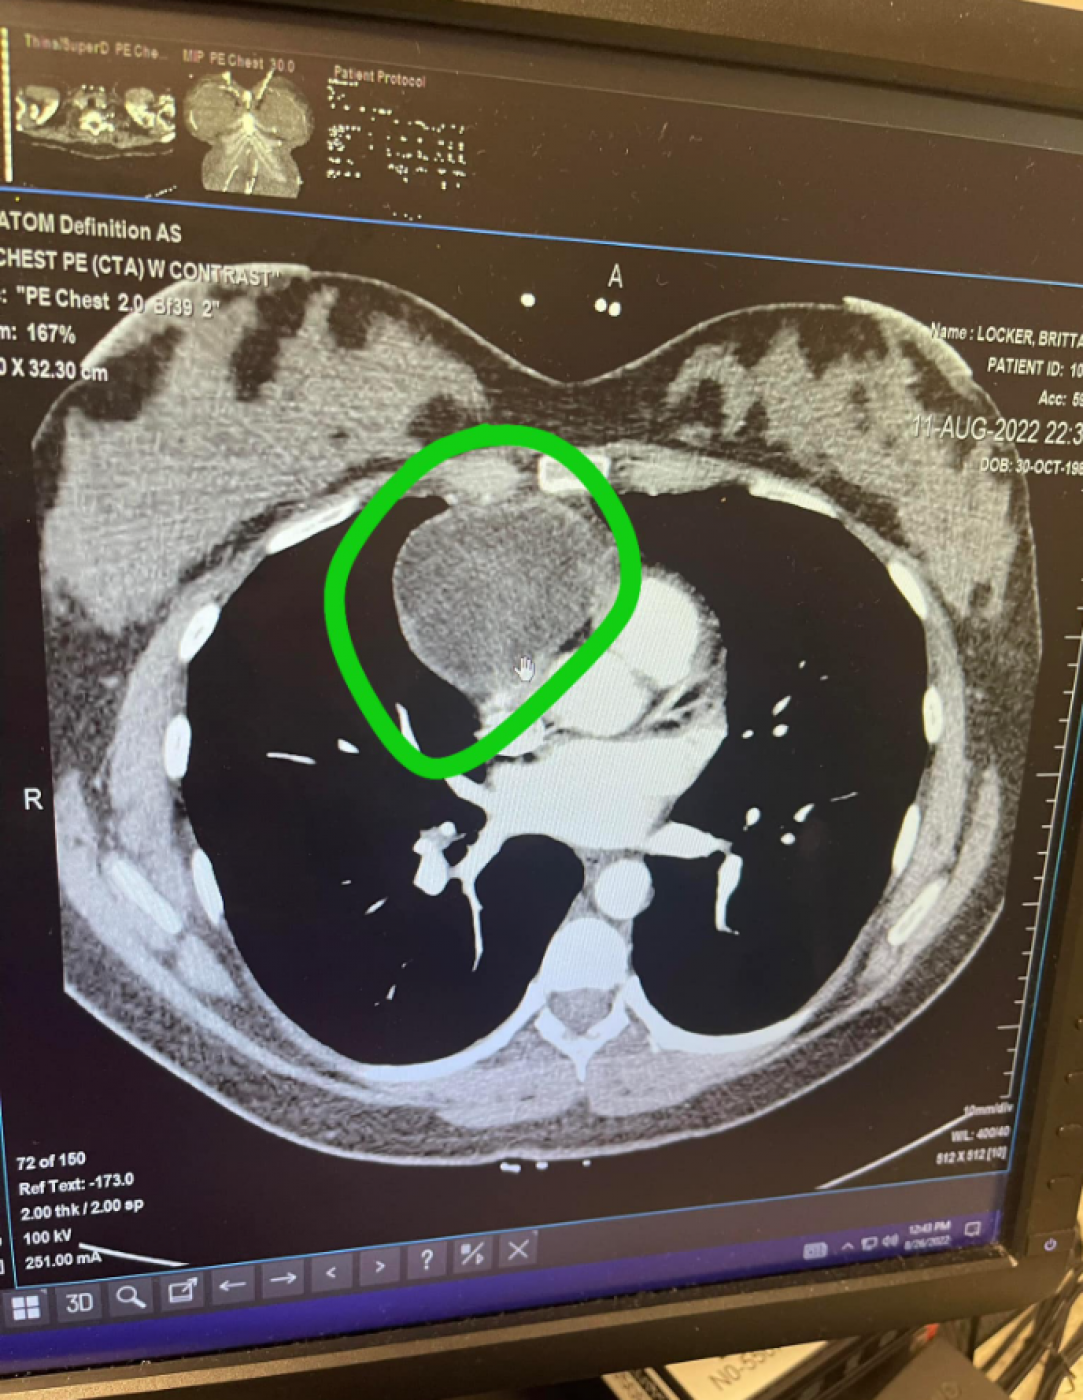

Posle snimaka skenerom lekari su mi objasnili da su pronašli veliku masu iznad srca, kao i da je moguće da se radi o tumoru.

- Tek kad su mi pokazali snimak shvatila sam ozbiljnost situacije. Nalaz magnetnom rezonancom je pokazao da masa pritiska 80 odsto mog srca. Jedini razlog zašto to nisam osećala jeste činjenica da sam bila trudna, a trudnice imaju dva dodatna litra krvi. Svaki doktor s kojim sam razgovarala mi je rekao da mi je Liv spasla život jer da nisam ostala trudna srce bi mi stalo i umrla bih - objasnila je Britani.